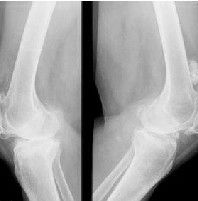

骨膜性軟骨瘤的X線上可見骨皮質上有表淺的碟形凹陷,偶呈多環狀,標以骨硬化線,不向髓腔延伸,有透鏡樣或半球狀的軟骨瘤團塊,有類似軟組織表現,偶有不透X線的顆粒和陰影,表示軟骨的鈣化和/或骨化。在軟骨瘤的周邊,被骨皮質頂起的骨膜可產生骨刺,包圍腫瘤的基部。